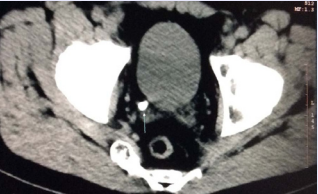

and a calculi in terminal ureter (Figure 3).

Figure 3 Abdominal CT. Calculi in left terminal ureter